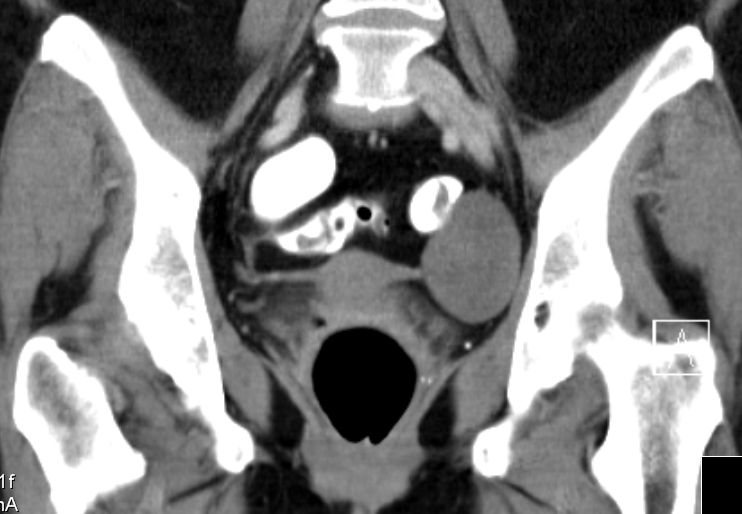

MRT sT2W TSE![]() | ||||